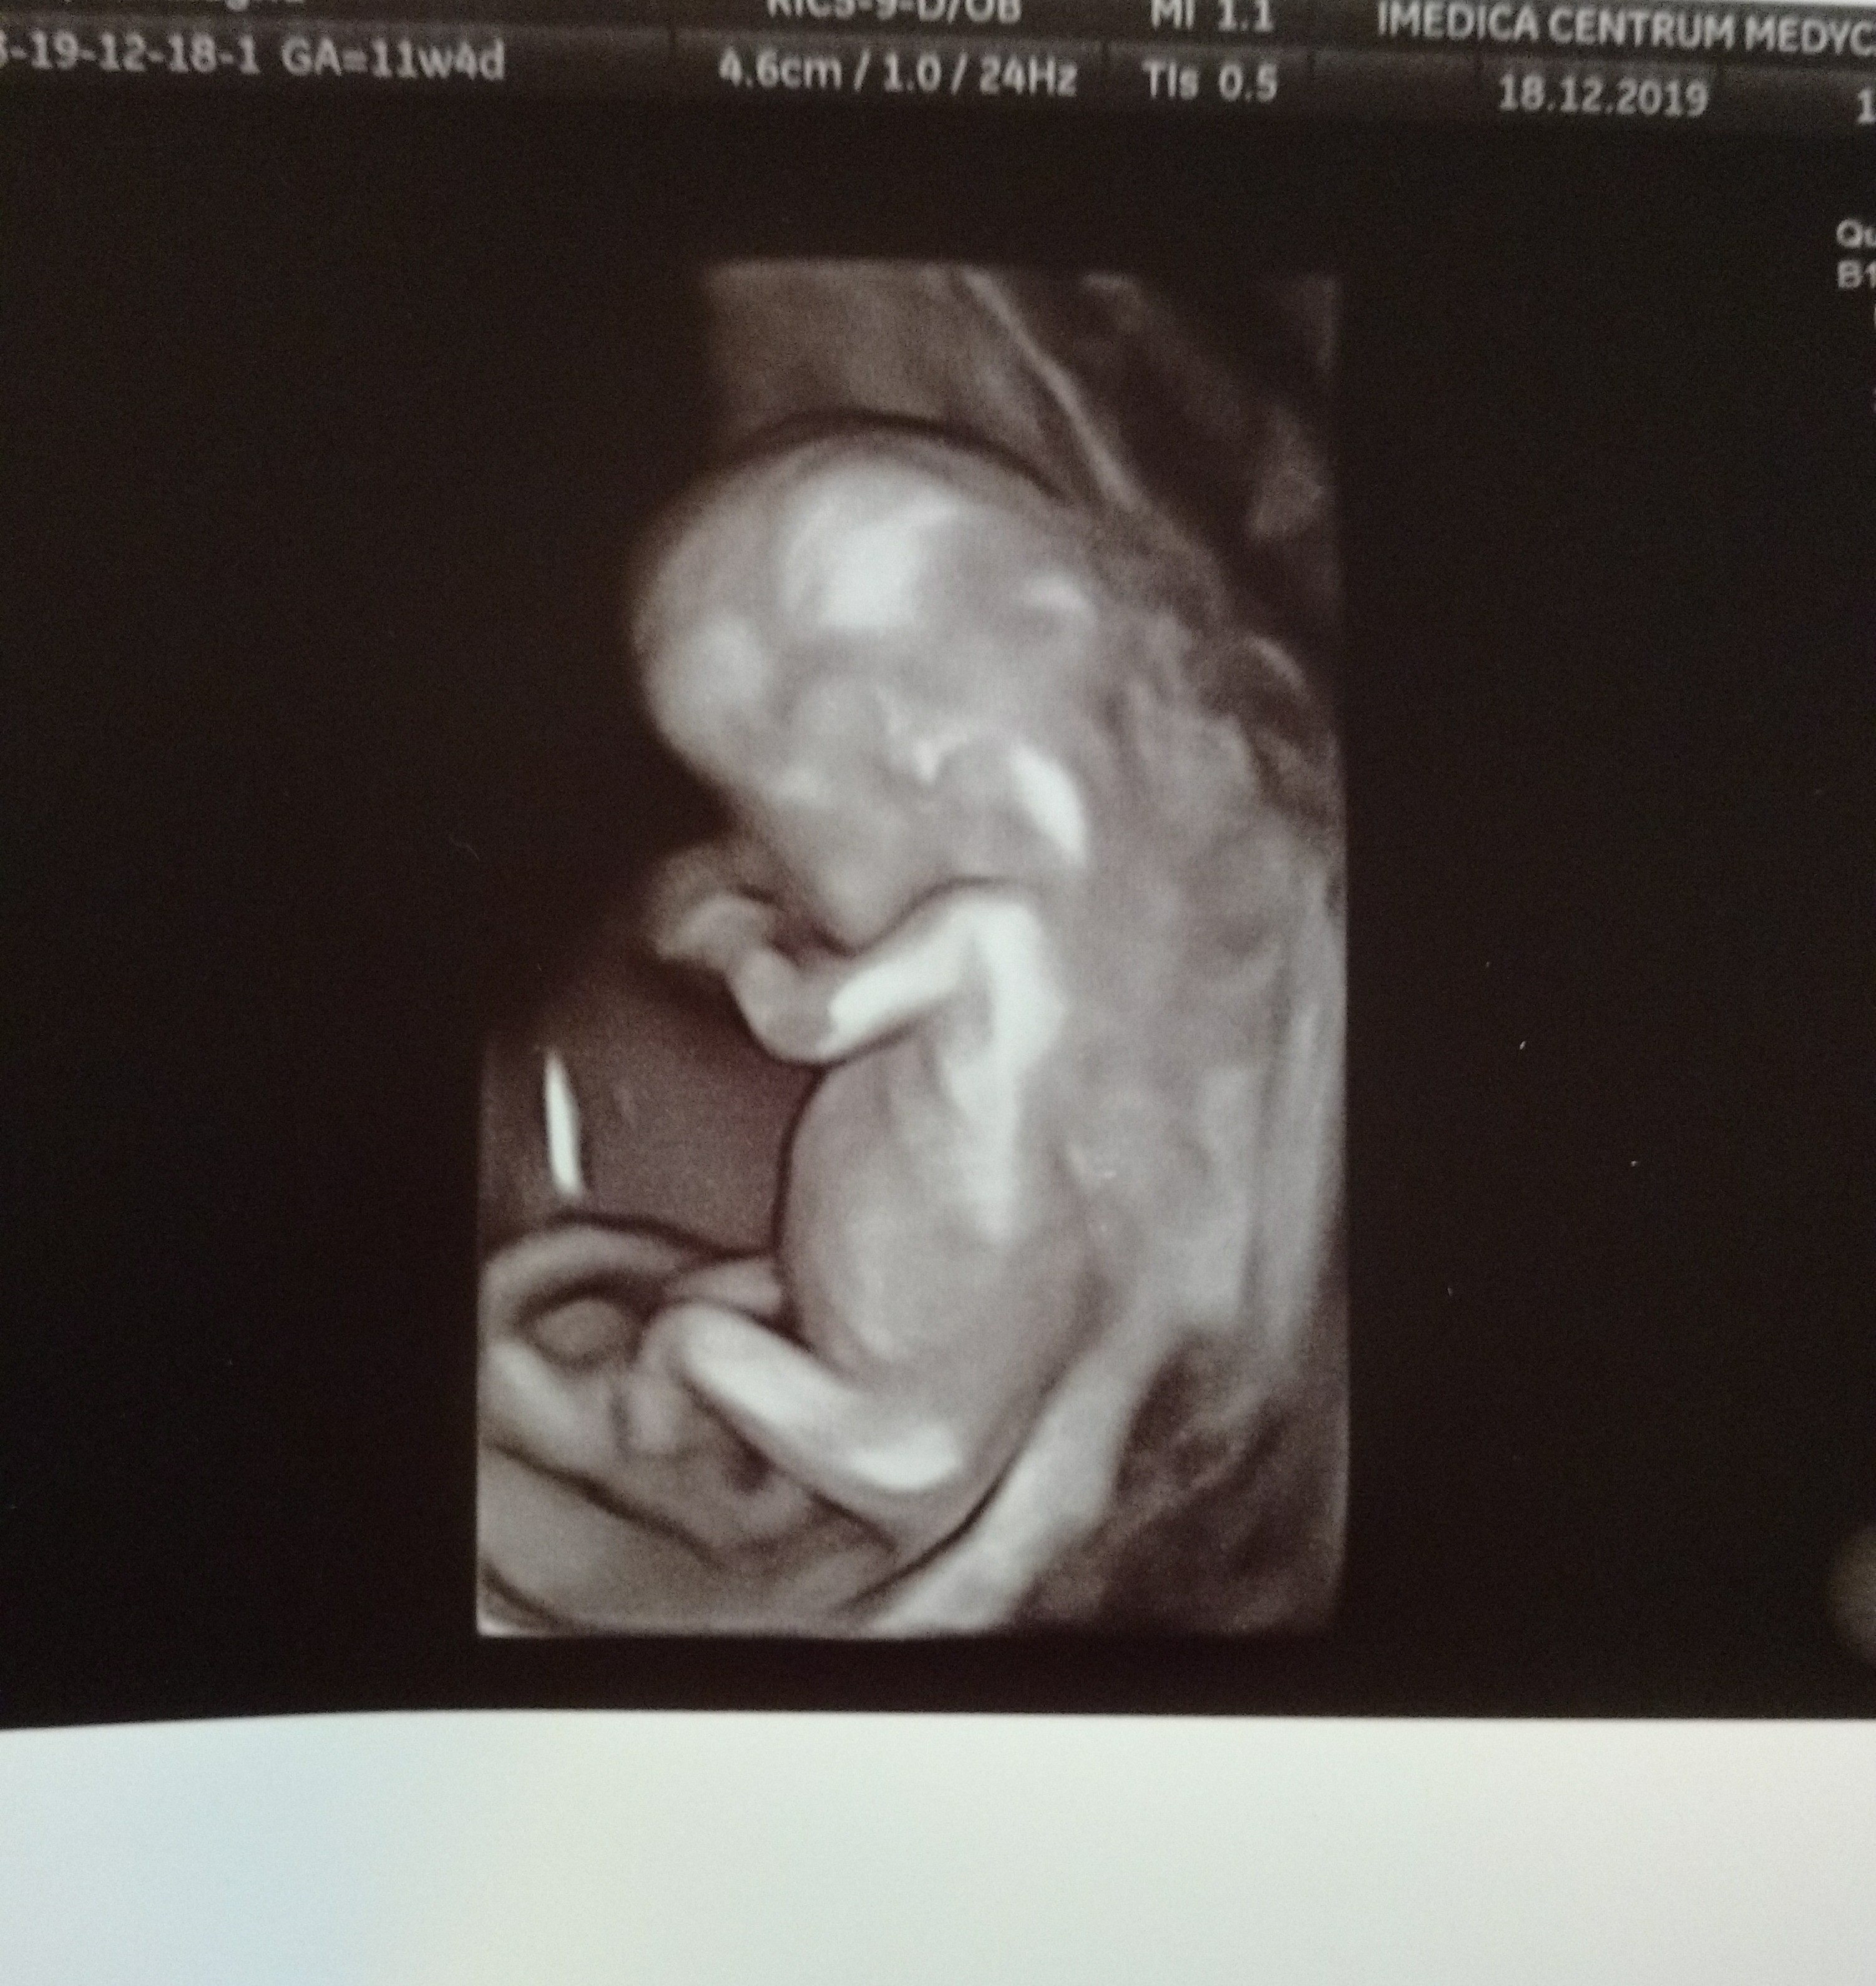

Jaki piekny widok. To jest prenatalne czy nie?cześć wpadłam tylko przynieść dobre wieściMoja dzidzia ma. się świetnie! 11+4.

Mi pow ze na ten wynik bede czekac 2 tygzdjęcie 3d

Ja mam jutro, już z wynikami pappa i stresuje się strasznie.zdjęcie 3d